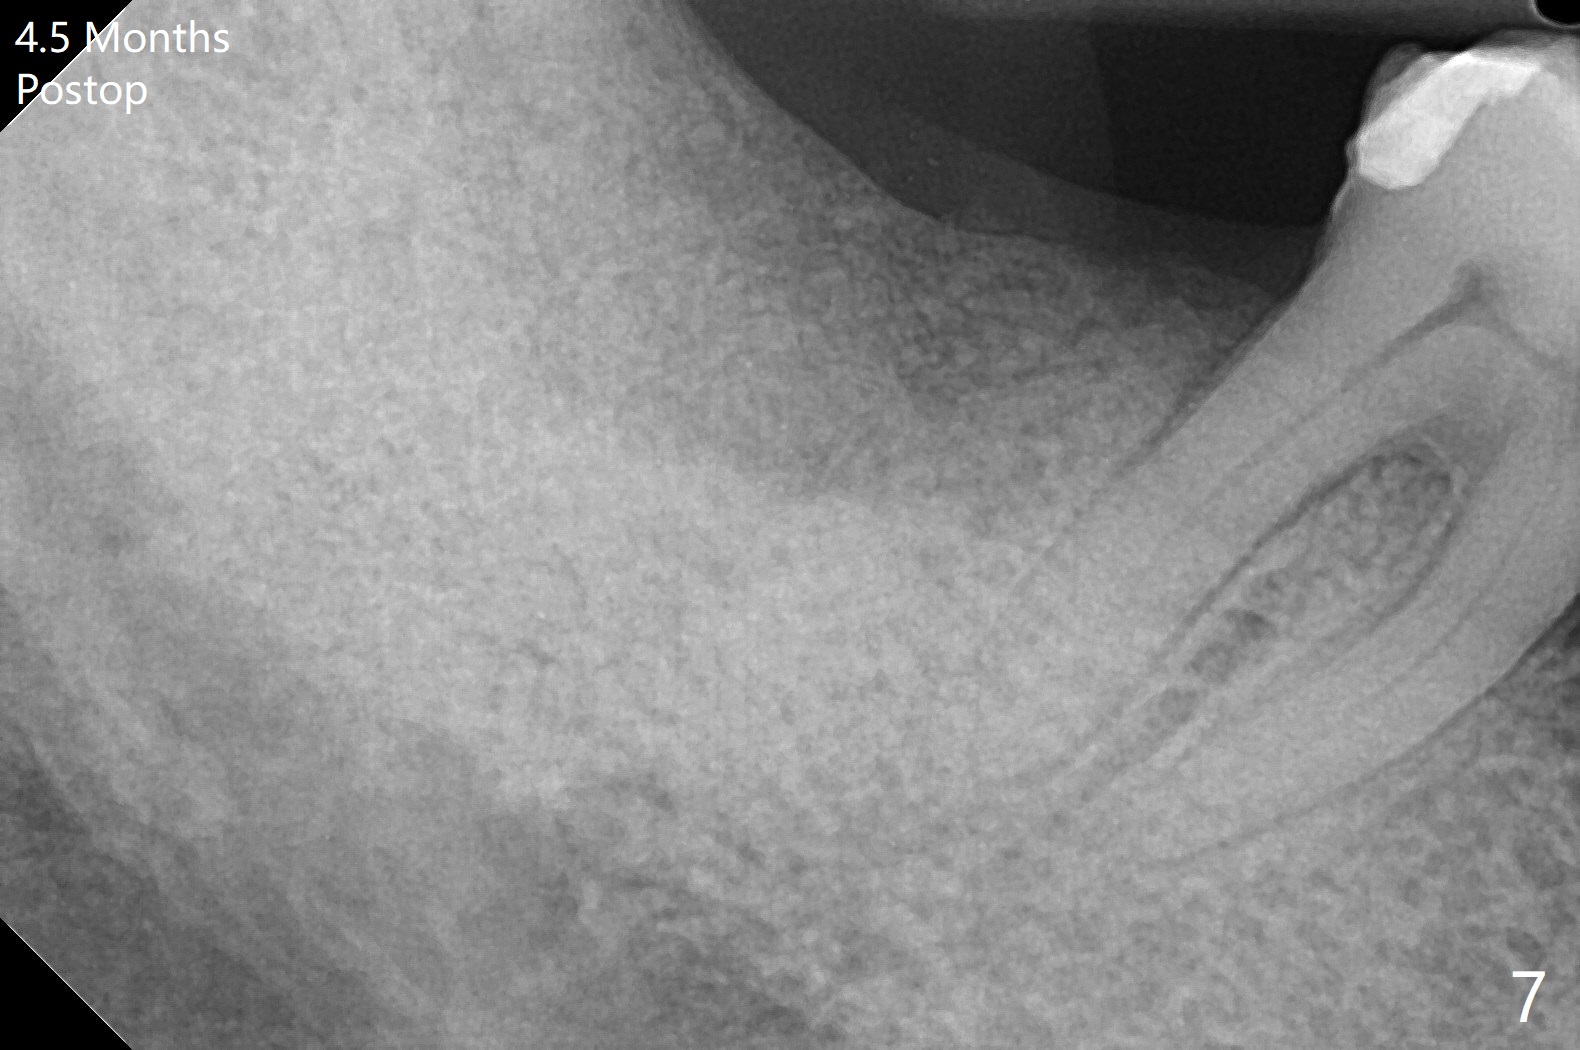

After removing the fractured apices of the tooth #31 (Fig.1,2), it is extremely difficult to start osteotomy with 7.3 mm stopper free hand. Since sticky bone (Fig.3,4) and PRF membrane are available, socket preservation is performed with bone condenser and PGA (Fig.5). If a surgical guide were fabricated, immediate implant would finish quicker. The socket opening is almost closed without pain or swelling 8 days postop (Fig.6). Clinically, the ridge is apparently wide with enough keratinized gingiva 4.5 months postop. The original ridge height seems to restore as the sticky bone undergoes condensation vertically (Fig.7, as compared to Fig.5). With bone graft, a 1.5 mm longer implant could be placed (Fig.8). The gingival pocket (Fig.9 white dashed line) seems to be an excellent cultivation bed for bone graft, although the latter also undergoes buccolingual shrinkage coronally (Fig.10).